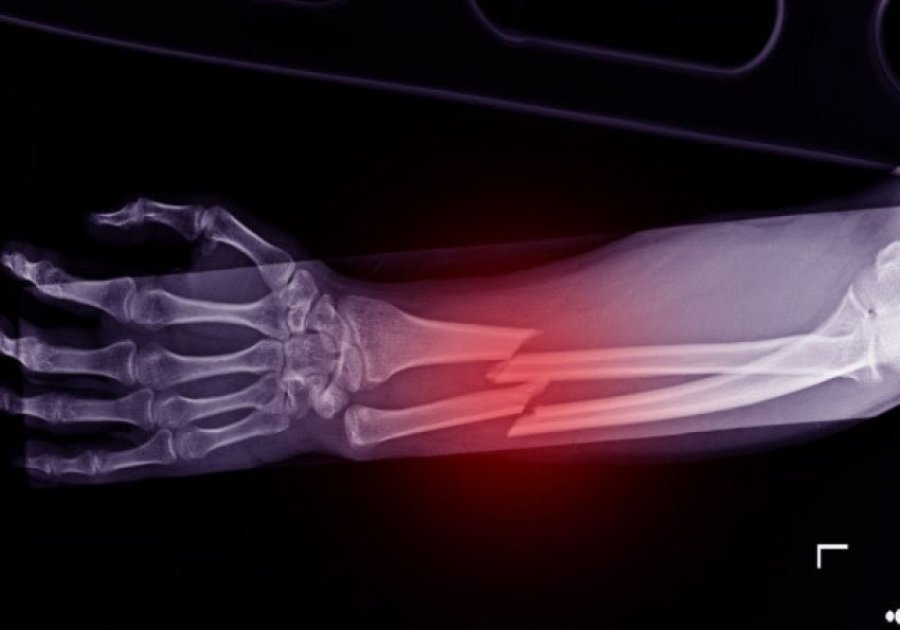

Shkencëtarët kinezë kanë zhvilluar një ngjitës kockash të ri të quajtur ”Bone-02”, që është i aftë të riparojë frakturat në vetëm tri minuta me një injeksion të vetëm, i frymëzuar nga mënyra se si ngjiten ostriket në kushte lagështie, shkruan italianstonic.it.

Ai siguron një lidhje shumë të fortë dhe tretet ndërsa kocka shërohet duke shmangur kështu përdorimin e pllakave metalike ose vidave.